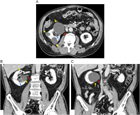

1. 片側の腰背部痛や側腹部痛では水腎症を念頭に置き、まず超音波検査を行い、尿路閉塞の位置と原因を同定するには単純CTを撮影する。